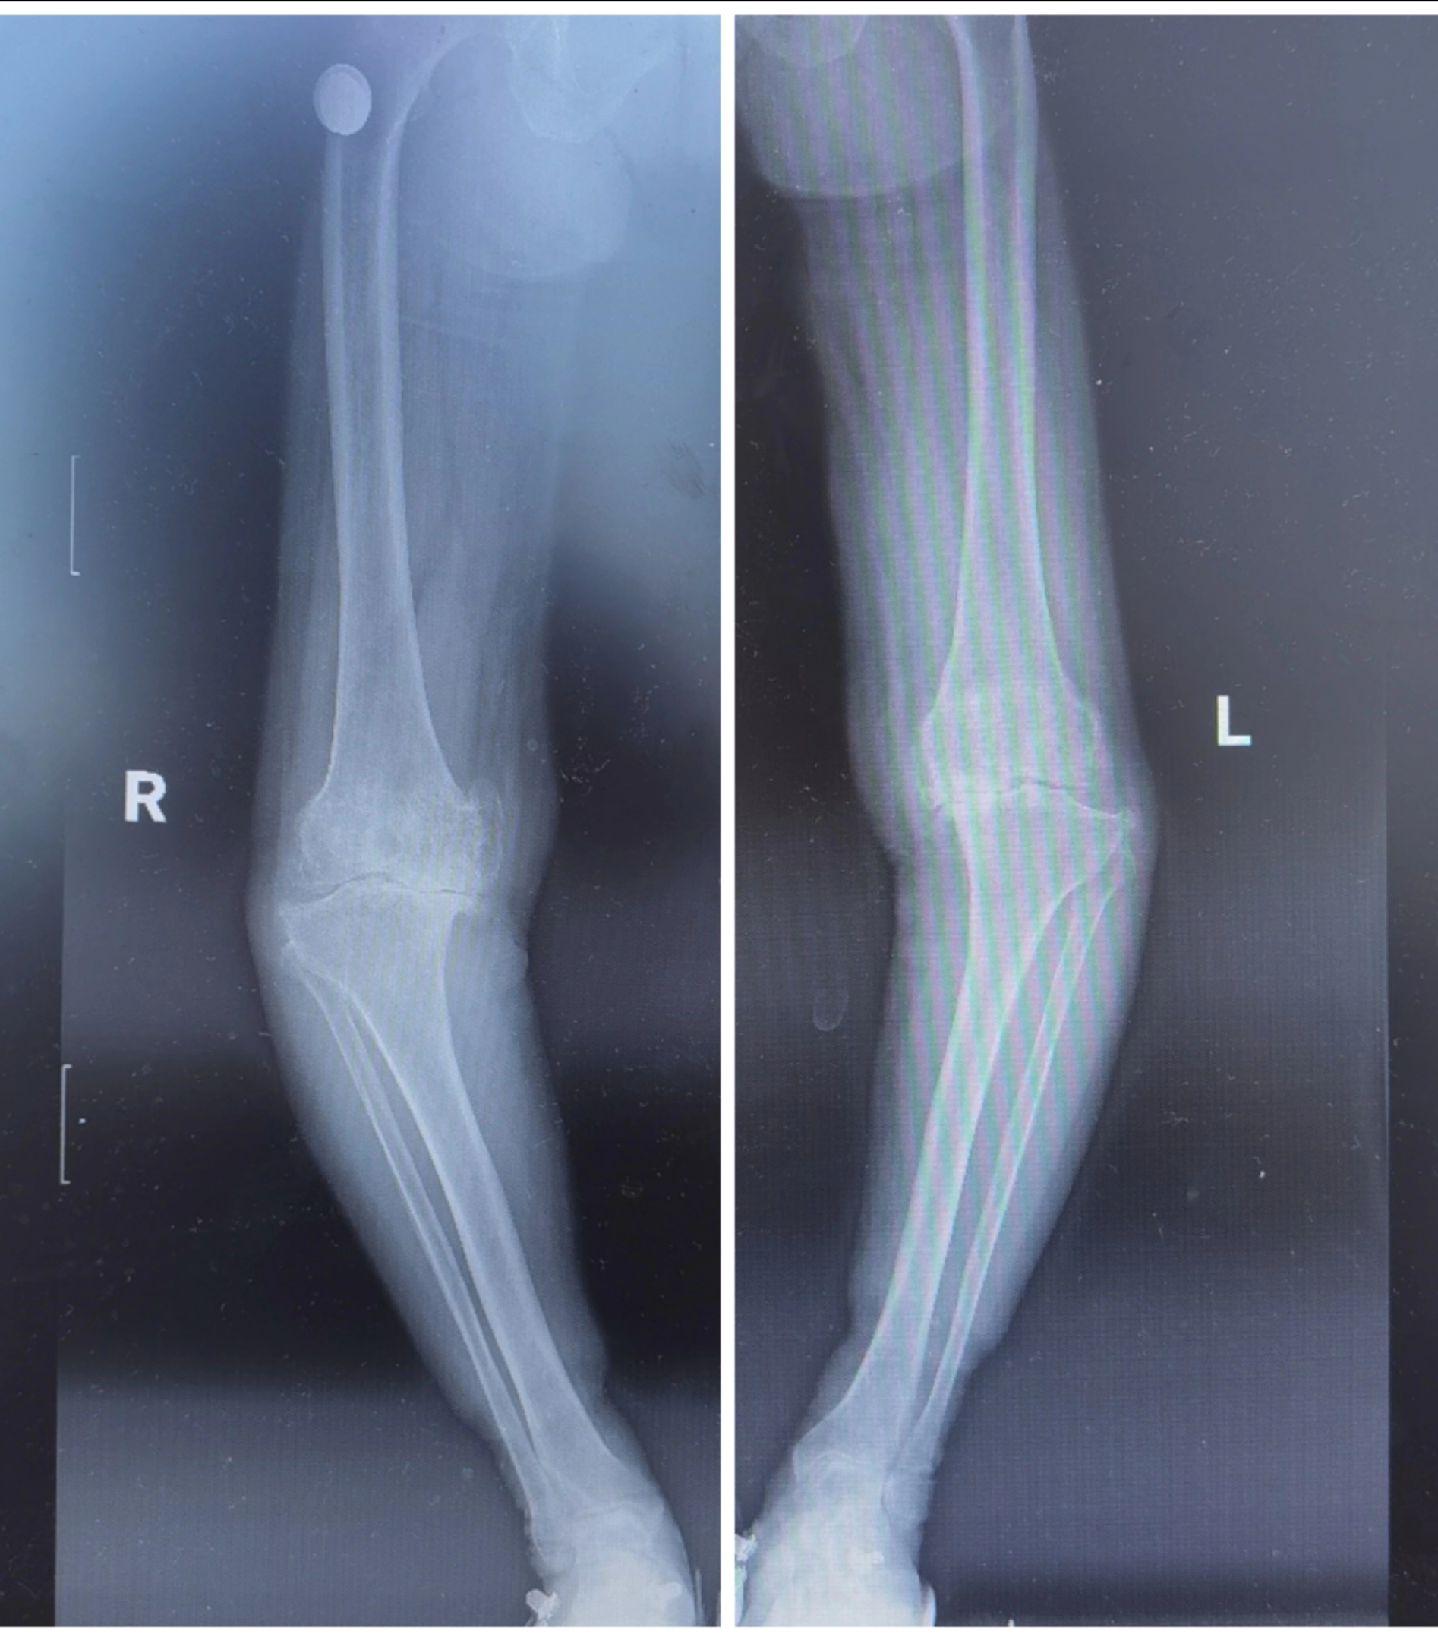

膝关节置换TKA.骨关节炎重度内翻合并屈曲挛缩畸形,无法行走,一期行双侧TKA,愿每一位患者都能得到有效的治疗,都能早日恢复正常生活🌹